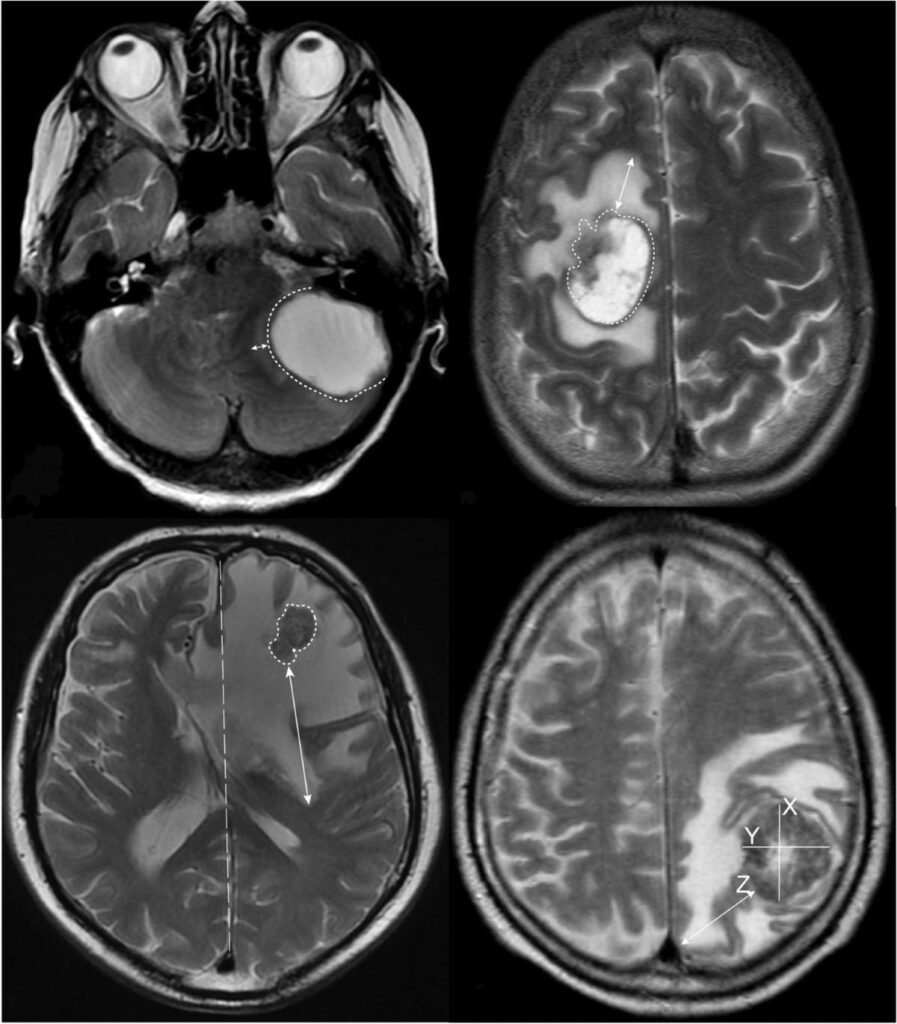

Ressonância Magnética (RM)

- Padrão Ouro: para detectar metástases cerebrais e espinhais.

- Realce com Gadolínio: essencial para caracterizar as lesões.

RMN DE ENCÉFALO: METÁSTASES CEREBRAIS